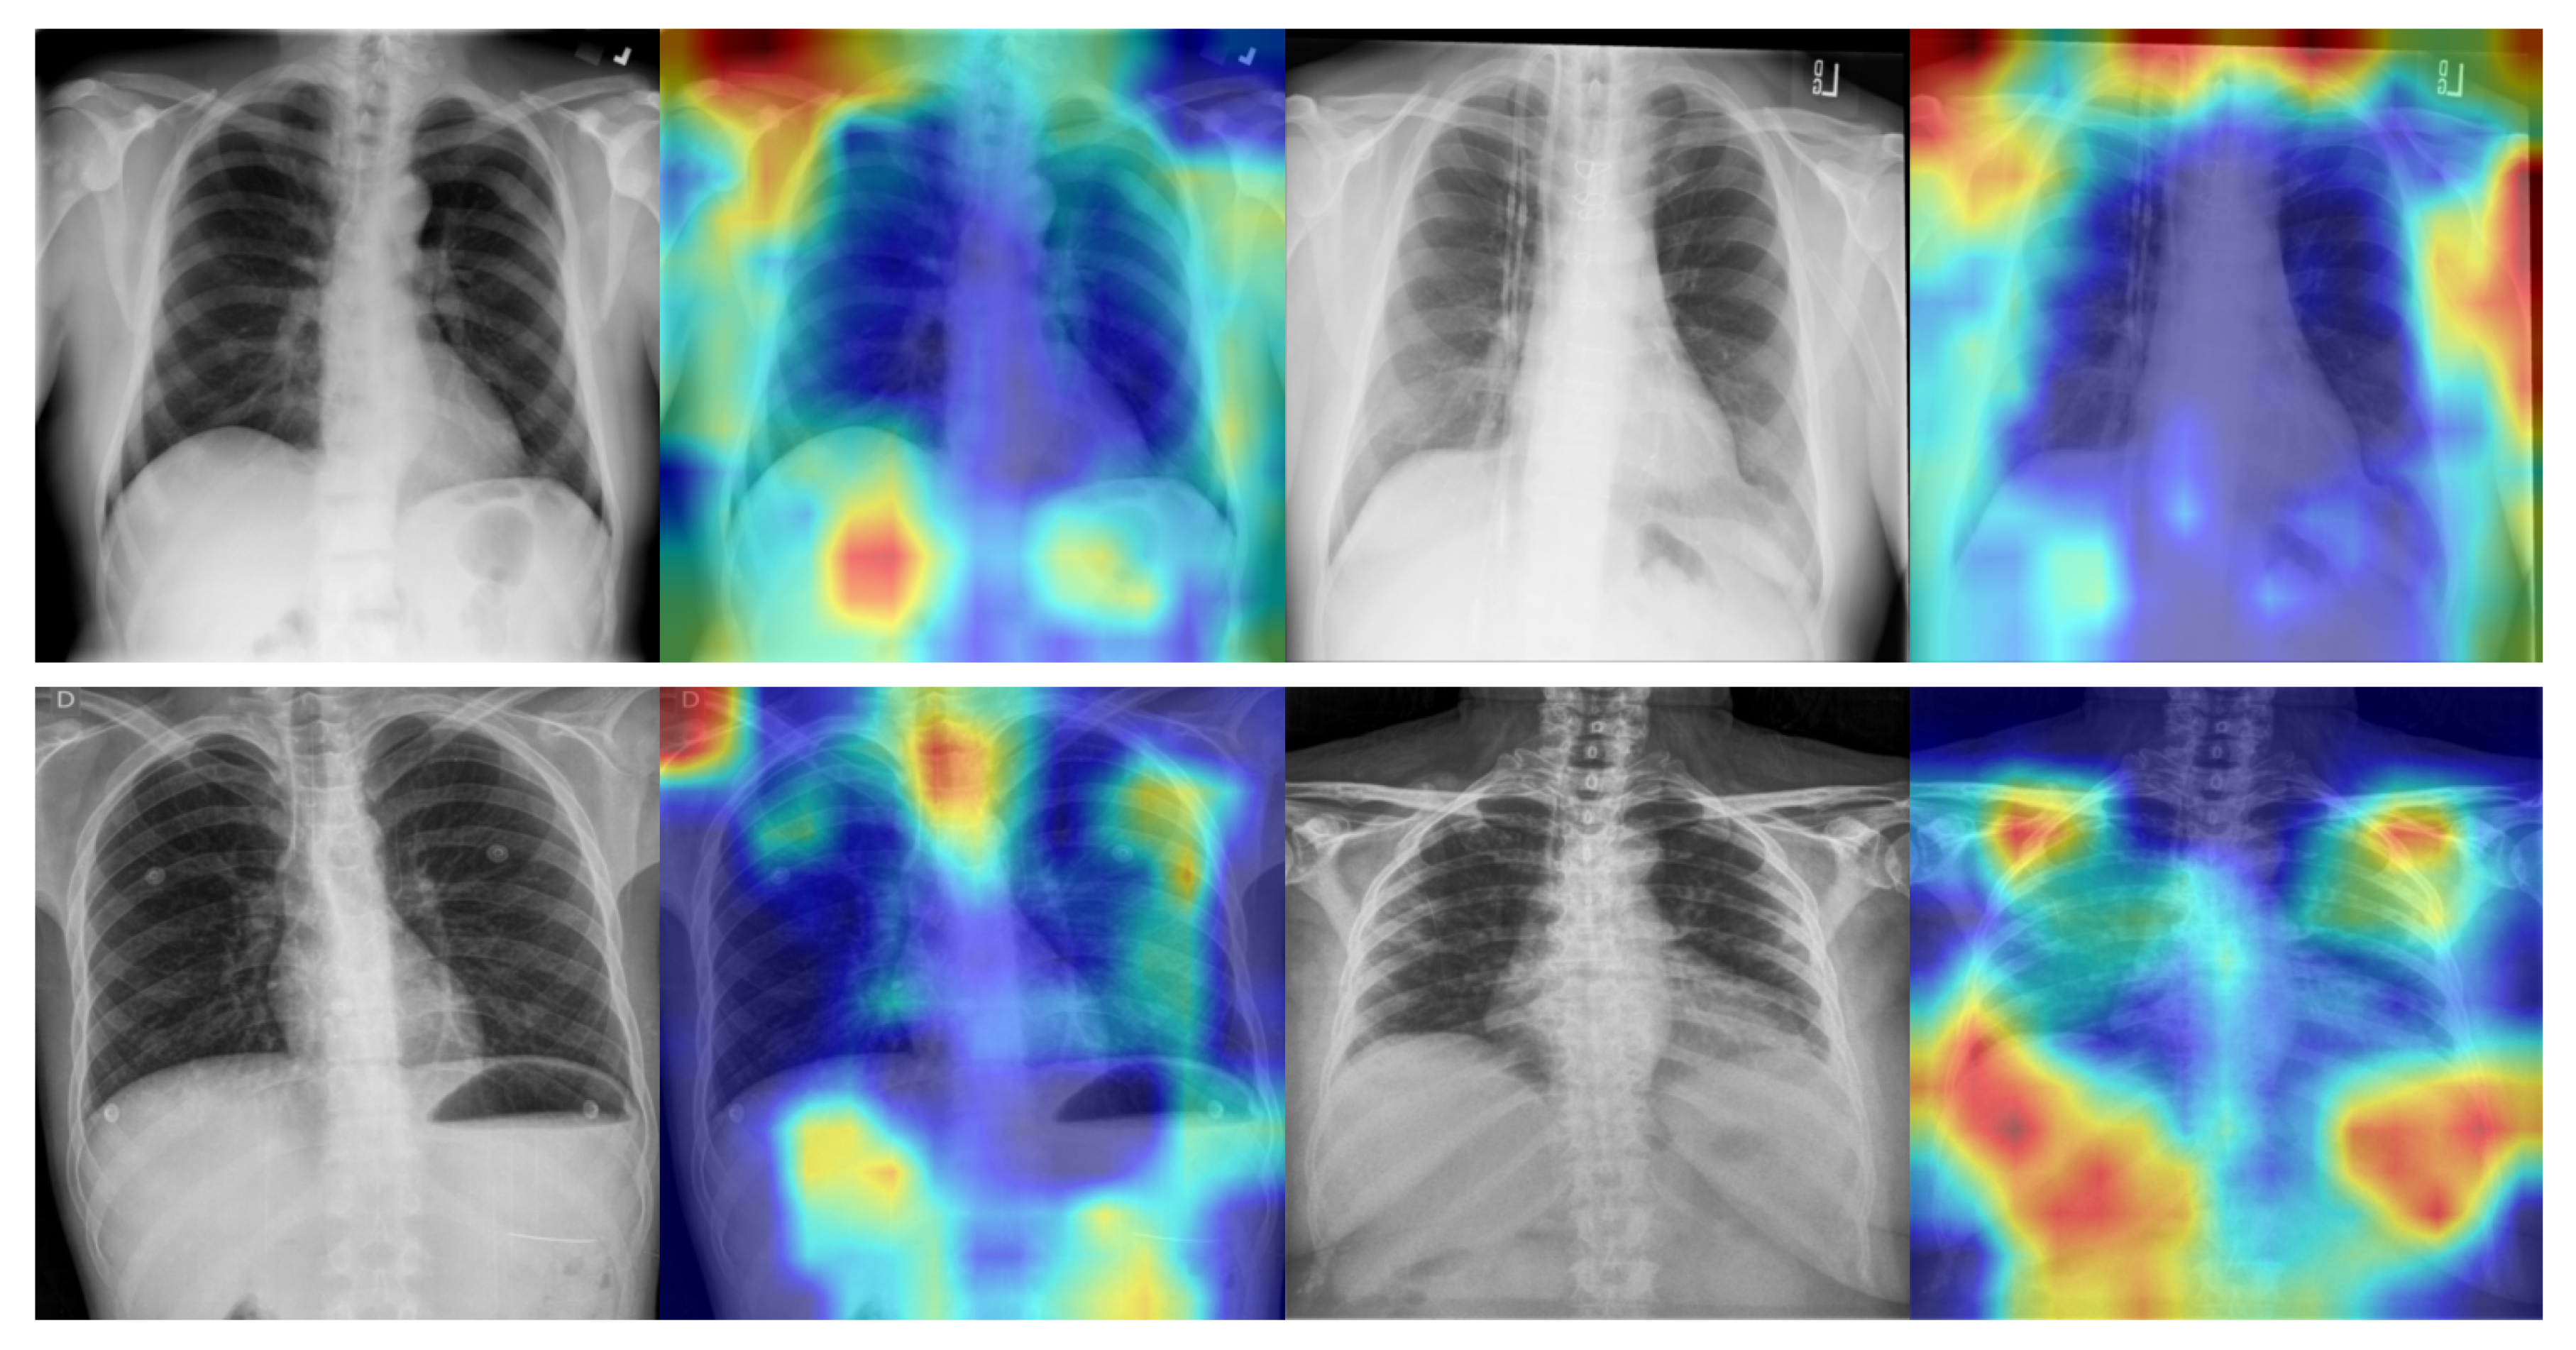

4.4. Qualitative Analysis

- Selvaraju, R.R.; Cogswell, M.; Das, A.; Vedantam, R.; Parikh, D.; Batra, D. Grad-CAM: Visual Explanations From Deep Networks via Gradient-Based Localization. In Proceedings of the IEEE International Conference on Computer Vision, Venice, Italy, 22–29 October 2017; pp. 618–626. [Google Scholar]